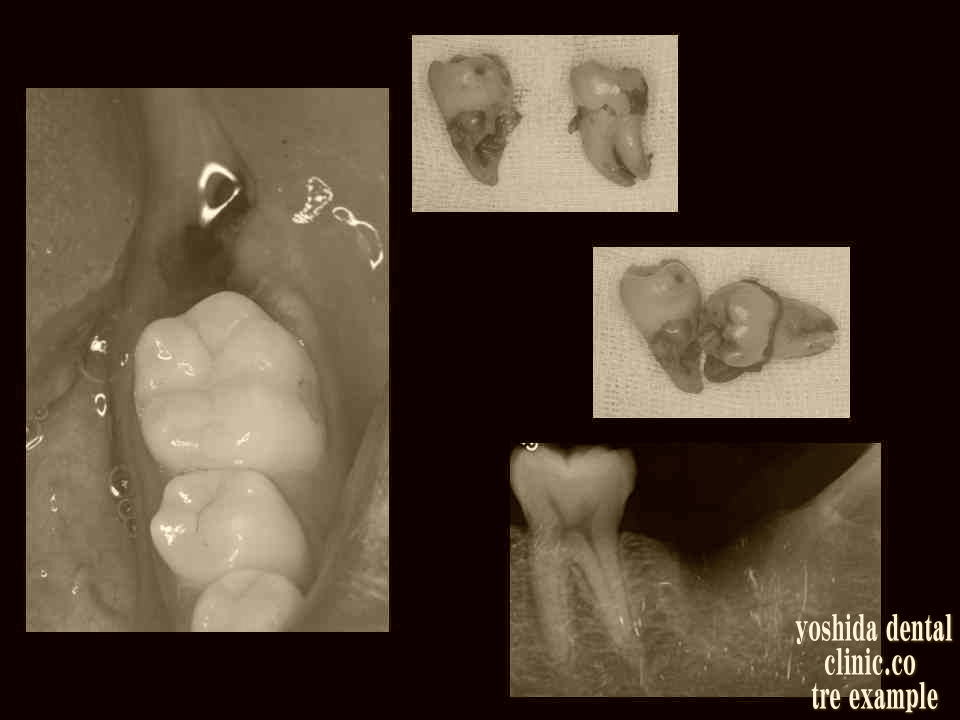

口腔内の歯牙腫瘍摘出術

歯牙腫瘍摘出前 歯牙腫瘍摘出後

右下の歯茎の中で歯が複数できる腫瘍確認 歯牙腫瘍を全て摘出しています。計5歯。

歯牙腫瘍摘出前 歯牙腫瘍摘出中歯牙腫瘍摘出後

左上の歯茎の中で歯が複数できる腫瘍確認 歯牙腫瘍を摘出後、計2歯。